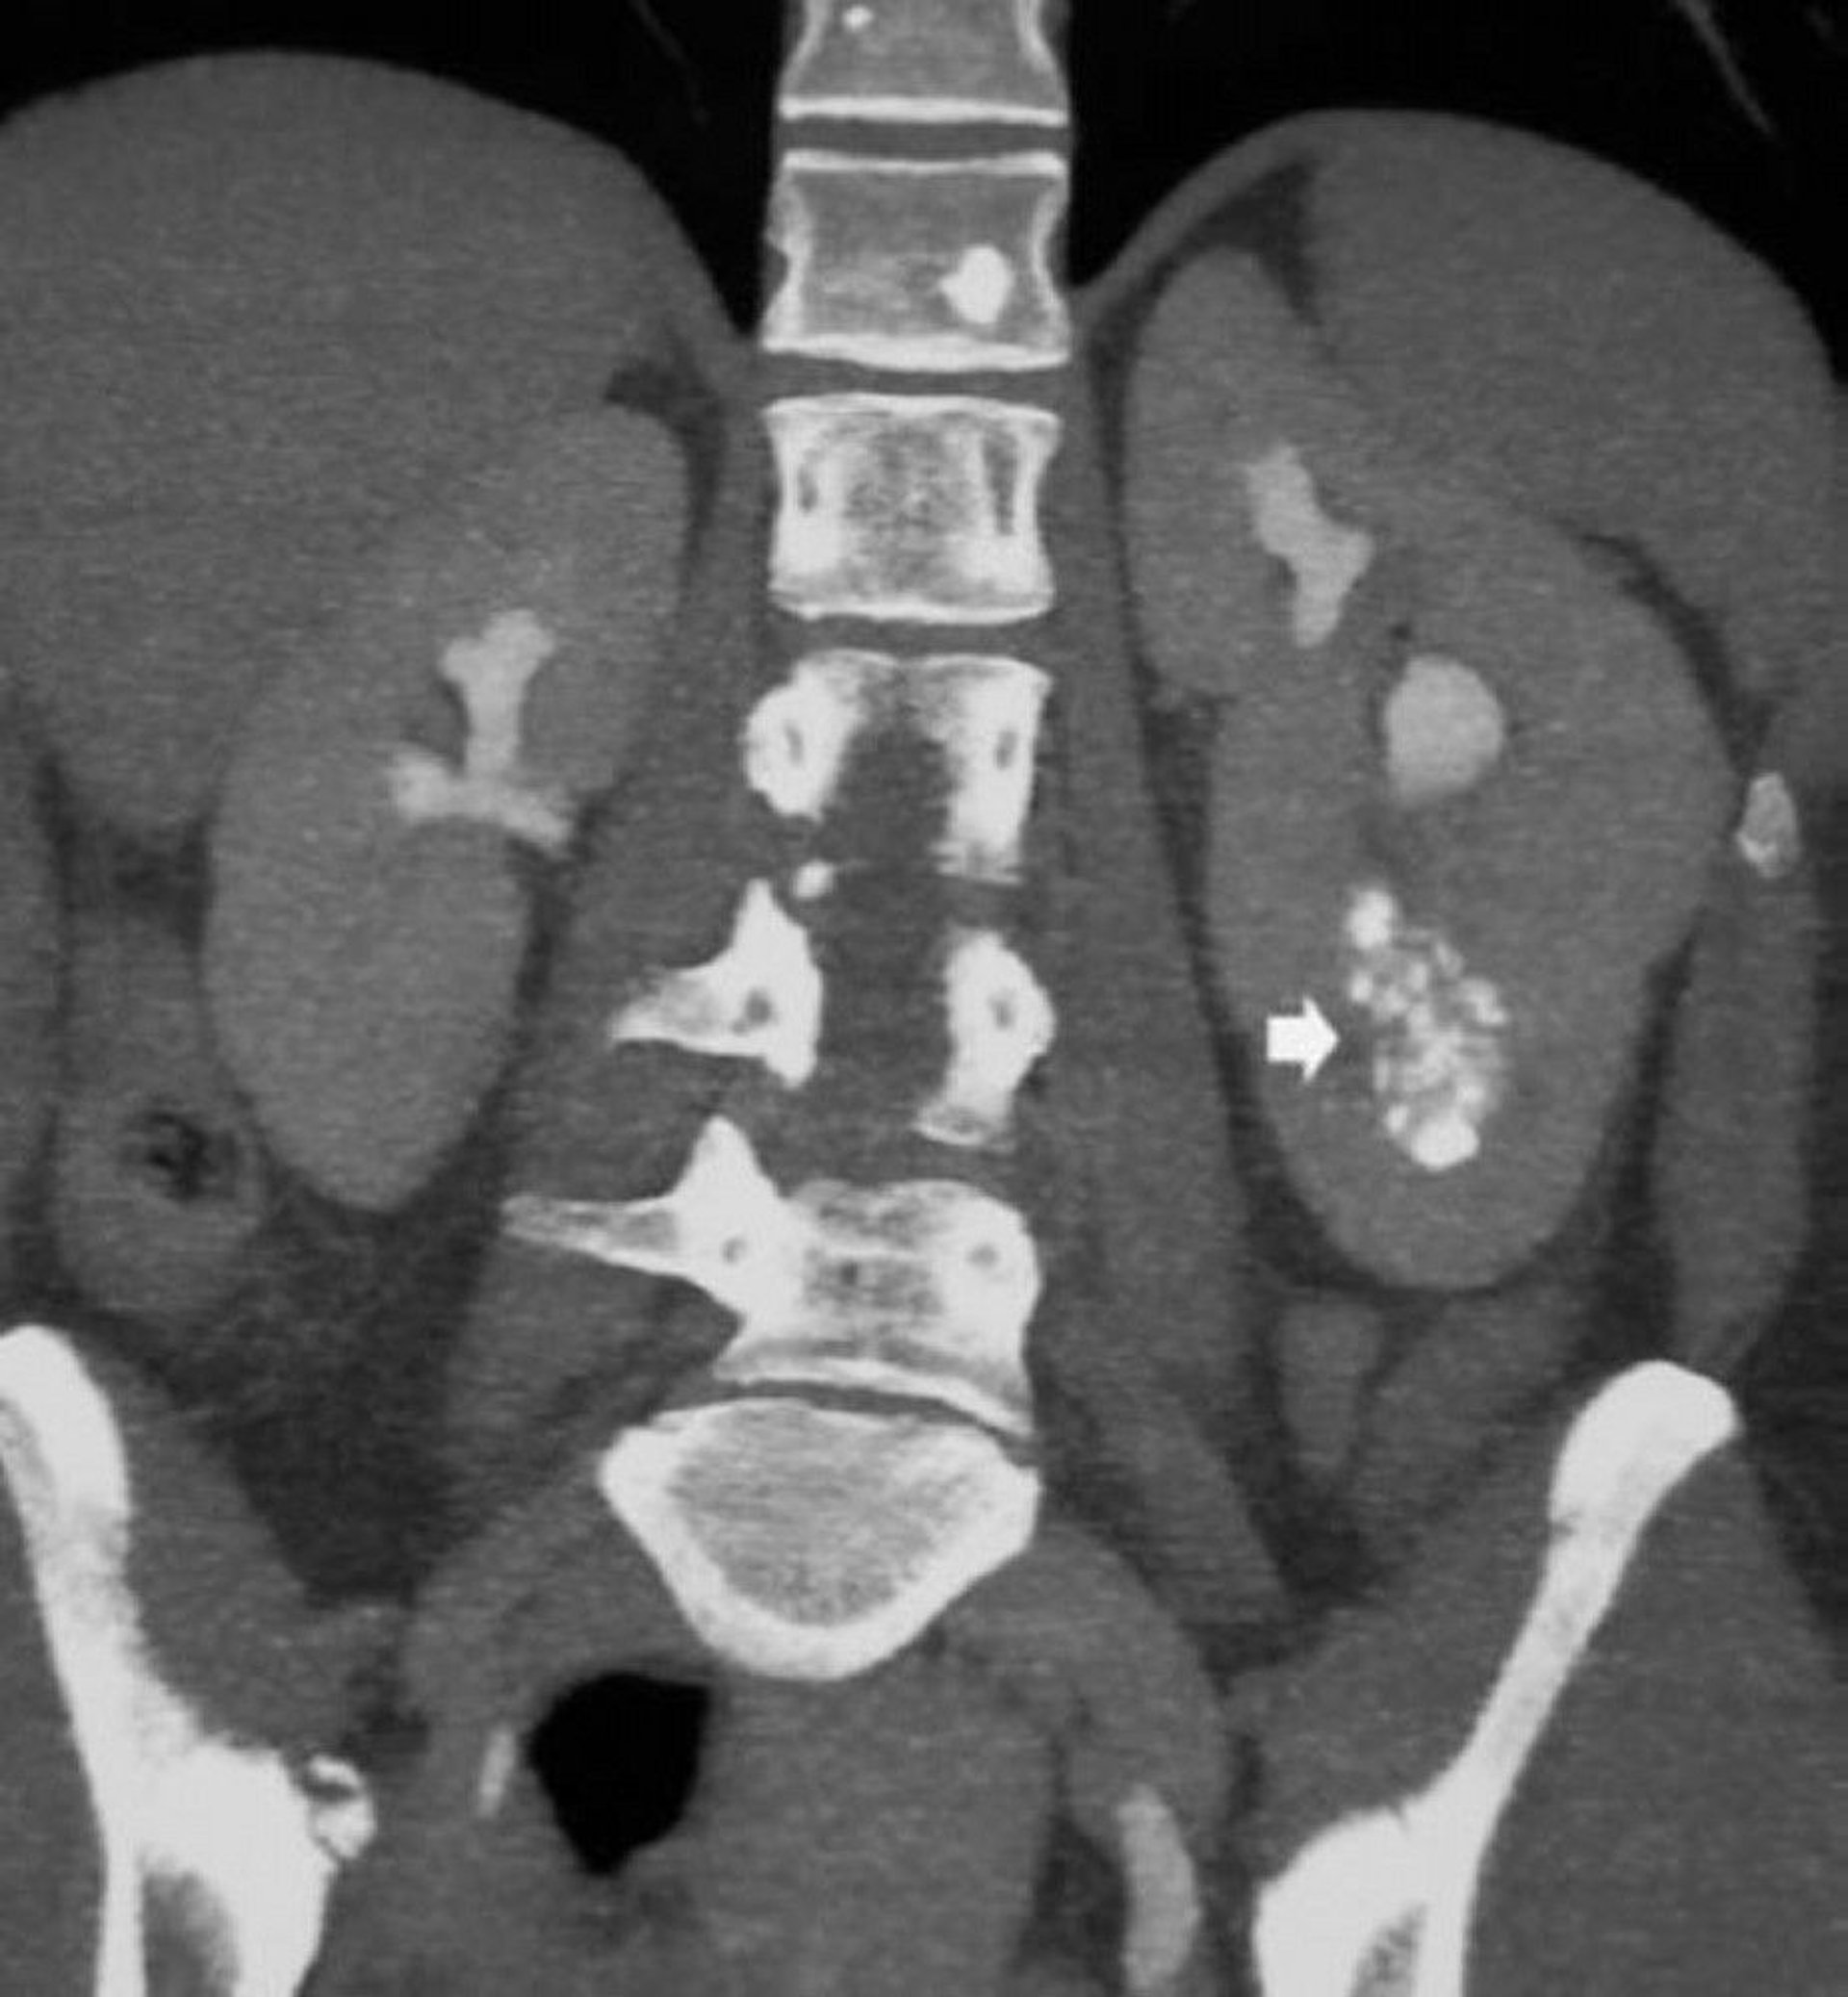

Noncontrast Coronal CT Scan Showing Medullary Nephrocalcinosis

This image shows medullary nephrocalcinosis and dilated contrast-filled collecting ducts in a patient with renal medullary sponge kidney (arrow).